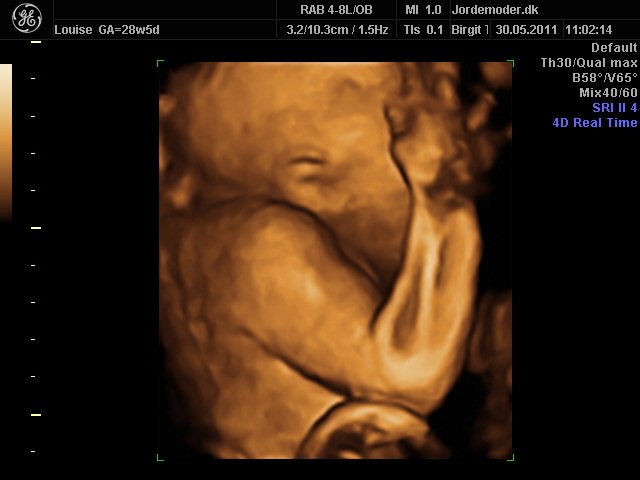

i uge 28

Vedhæftede fotos (klik for at se i fuld størrelse)